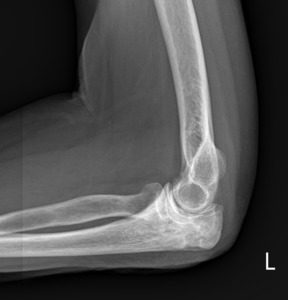

A physical exam performed by the orthopedist was noted to show soft tissue swelling at the proximal ulna, about 2 cm distal to the olecranon tip. There was minimal erythema and no tenderness to palpation. Due to the location of soft tissue swelling just distally to the olecranon tip, the orthopedic surgeon wanted to rule out involvement of the ulnar bone in this case. X-rays obtained and interpreted by the orthopedist demonstrated a moth-eaten appearance of the proximal ulna (Figure 1). With radiographic findings concerning for osteomyelitis versus neoplasm, an MRI was ordered.